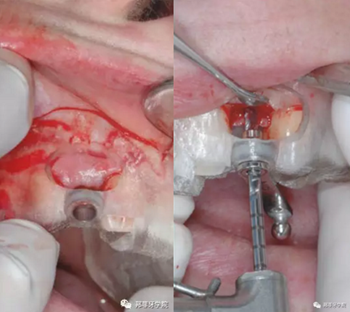

本病例中,缺隙足夠在保持天然牙與植體之間最小距離1.5mm的情況下兩側(cè)各植入1枚3.5mm Nobel Replace Tapered Groovy植體。手術(shù)導(dǎo)板設(shè)計頰側(cè)開窗,方便操作及固位。采用嵴頂切口,翻粘骨膜瓣(圖5 & 6)。

圖5 & 6:手術(shù)導(dǎo)板頰側(cè)開窗設(shè)計

采用手術(shù)導(dǎo)板進行備洞及植入,植入扭矩35Ncm。植體適當(dāng)偏腭側(cè)植入,避免鄰近結(jié)構(gòu)破壞及前庭處骨外壁穿孔。植體肩臺位于鄰牙釉牙本質(zhì)界根尖方2mm(圖7&8)。

圖7 & 8:導(dǎo)板下備洞及植入